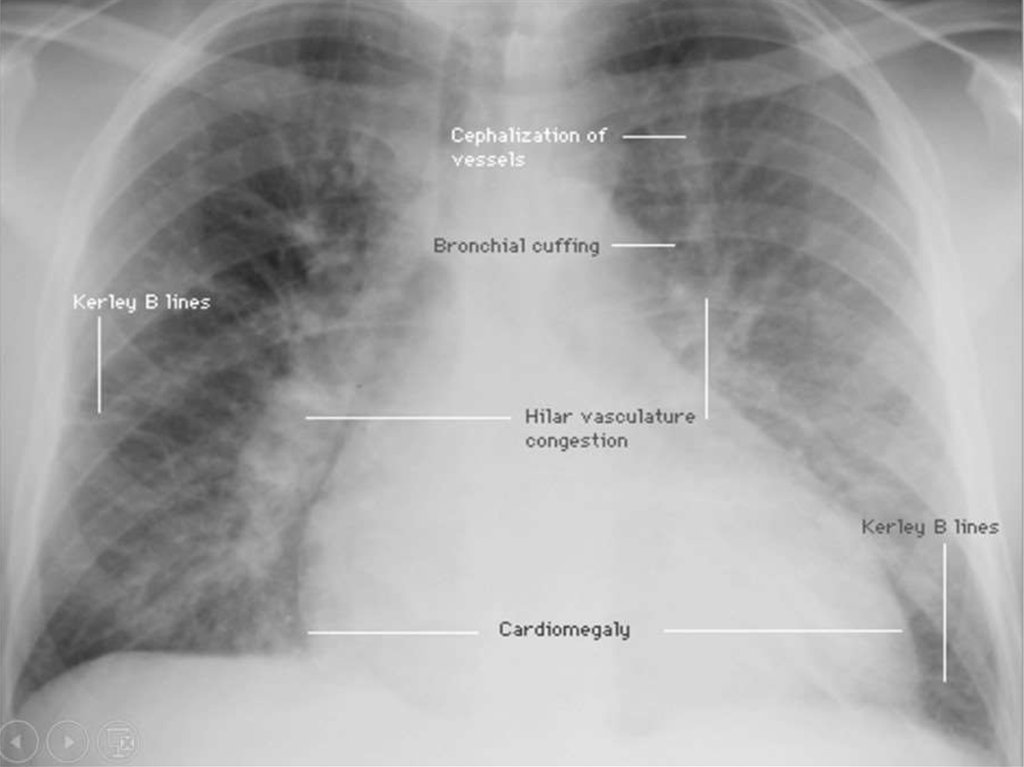

6. Основные звенья патогенеза ОРДС

• Развитие ранних признаков повреждения

легких.

• Развитие некардиогенного отека легких.

• Нарушение микроциркуляции в легких.

• Клеточные реакции, с

иммунокомпетентными клетками.

7. Патогенез

• В основе патогенеза ОРДС лежит повреждение

эндотелия микроциркуляторного русла легких и

альвеолярного эпителия, их базальных мембран,

эндогенными и экзогенными факторами агрессии

• Это ведёт к нарушению микроциркуляции в легких,

повышению проницаемости легочных капилляров,

развитию некардиогенного отека легких